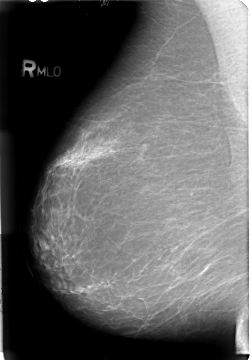

B_3018_1.RIGHT_MLO

RIGHT_MLO LINES 4680 PIXELS_PER_LINE 3264 BITS_PER_PIXEL 12 RESOLUTION 50 NON_OVERLAY